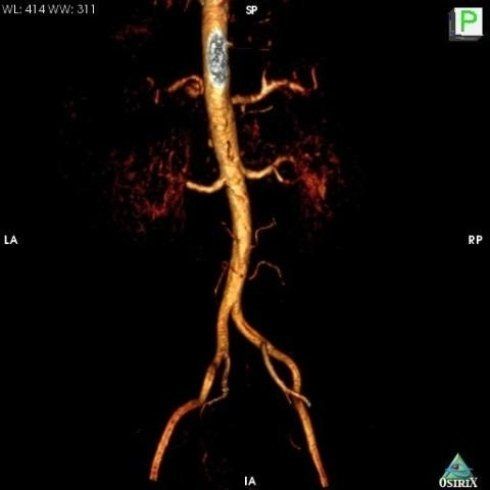

TC MULTISTRATO A BASSA DOSE (64 STRATI)

• Angio Tc Aorta